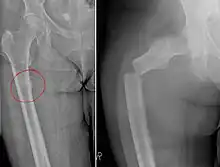

Chalkstick fracture due to bone metastasis of breast cancer. Left image shows the metastasis, on the right a pathological fracture a few days later.

Chalkstick fractures are fractures, typically of long bones, in which the fracture is transverse to the long axis of the bone, like a broken stick of chalk.[1] A healthy long bone typically breaks like a hard woody stick as the collagen in the matrix adds remarkable flexibility to the mineral and the energy can run up and down the growth rings of bone. The bones of children will even follow a greenstick fracture pattern.

Chalkstick fractures are particularly common in Paget's disease of bone, and osteopetrosis.[2] It is also seen in cases of fused spine as in a patient with ankylosing spondylitis.[3]